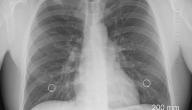

يُعرَف التهاب القصبات أو الشُعب الهوائيّة بأنّه تهيُّج في الأنسجة المُبطّنة للأنابيب التي تُمرّر الهواء من الفَم والأنف وصولًا إلى الرئتين. وغالبًا ما يتكيّف الأشخاص ممّن يُعانون من التهاب الشعب الهوائيّة مع استعمال كميّة قليلة من الأُكسجين، إضافةً إلى معاناتهم من وجود المُخاط والبلغم في مجاري التنفس لديهم، وعدم قدرتهم على تنظيفها. ويقسّم التهاب الشعب الهوائيّة قسمين اثنين: أحدهما حاد والآخر مُزمن.

غالبًا ما تتسبّب الفيروسات في الإصابة بالتهاب الشعب الهوائيّة الحاد؛ كالبَرد، والإنفلونزا، إضافةً إلى إمكانيّة حدوث الالتهاب في الشعب الهوائيّة بسبب عدوى بكتيريّة، والتعرُّض لبعض المواد التي قد تُهيِّج الشعب الهوائيّة وتُمرضها؛ مثل: الغبار، والعطور، والأبخرة، والهواء المُلوّث. أمّا النوع الثاني فهو التهاب الشعب الهوائيّة المُزمن، وينجم عن تهيُّج الرئة والأنسجة الموجودة داخلها وتدميرهما. ويُعدّ التدخين أكثر الأسباب شُيوعًا للإصابة بهذا النوع من الالتهابات، ويؤدّي أيضًا طول التعرُّض لبعض المُلوّثات الأُخرى؛ مثل: الأغبرة، والمواد العطريّة إلى إحداث أضرار أيضًا بالشُعَب الهوائيّة.[١]

يُمكن أن تظهر بعض الأعراض المُرافقة لالتهاب الشعب الهوائيّة المُزمن بعد مدة طويلة من التهاب هذه الأنابيب الهوائيّة؛ كأن يُعاني الشخص المُصاب من سُعال قوي ومُستمر قد يترافق مع خروج مُخاط أصفر، أو أخضر أو أبيض من الرئتين. ومع مرور الوقت واستمرار الإصابة فإنّ كمية المُخاط تزداد تدريجيًّا نتيجة ارتفاع إنتاجها في الرئتين، ممّا قد يتسبّب في زيادة تراكمها في القصبات الهوائيّة، وبالتالي إعاقة مرور الهواء مع الوقت، ثمّ صعوبة في التنفُّس، قد يترافق هذا الضِيق أو الصعوبة في التنفُّس مع الصفير الذي قد يُصبح أوضح أثناء ممارسة الأنشطة الرياضية. وقد تشتمل الأعراض الأُخرى التي قد يشعر بها الشخص المُصاب بالتهاب الشعب الهوائيّة المُزمن على:[٢]

عند تفاقُم الأعراض وازديادها شدة فإنّ المريض قد يبدأ لون جلده وشفتيه بالتغيُّر ليُقارب اللون الأزرق؛ نتيجة نقصان تغذية الجسم بالأُكسجين الموجود في الدم، ممّا قد تنجُم عنه مجموعة من المشاكل الأُخرى؛ مثل: انتفاخ في الساقين والكاحلين، أو الاستسقاء الطّرفي.